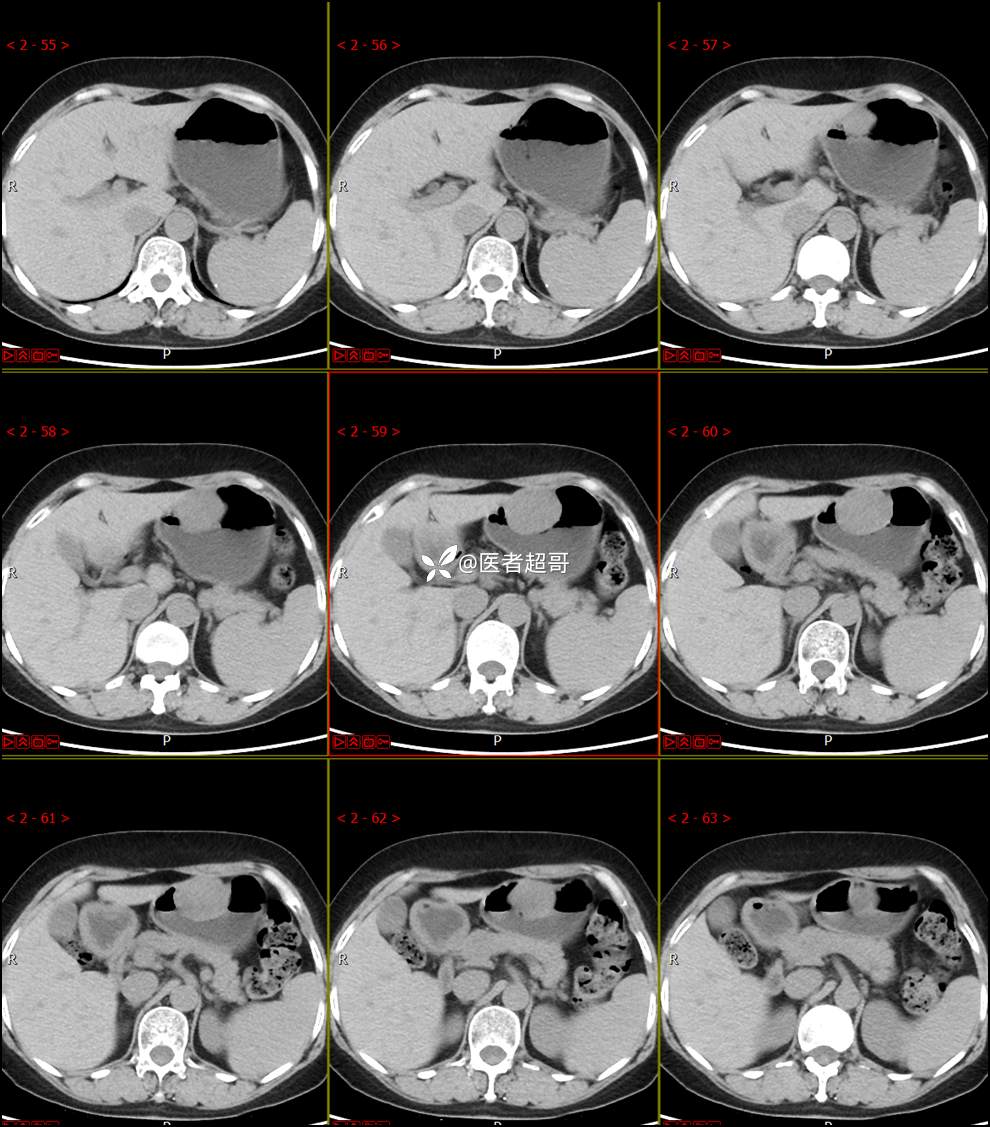

【影诊笔记759】胃体巨大隆起,间质瘤?神经鞘瘤?平滑肌瘤?请鉴别诊断!有结果!

患者半月前无明显原因及诱因出现上腹部疼痛不适,以夜间腹痛为主,无放射性疼痛,间断嗳气,无反酸烧心,无腹泻黑便,于我院门诊行胃镜显示:胃体前壁巨大隆起型病变。